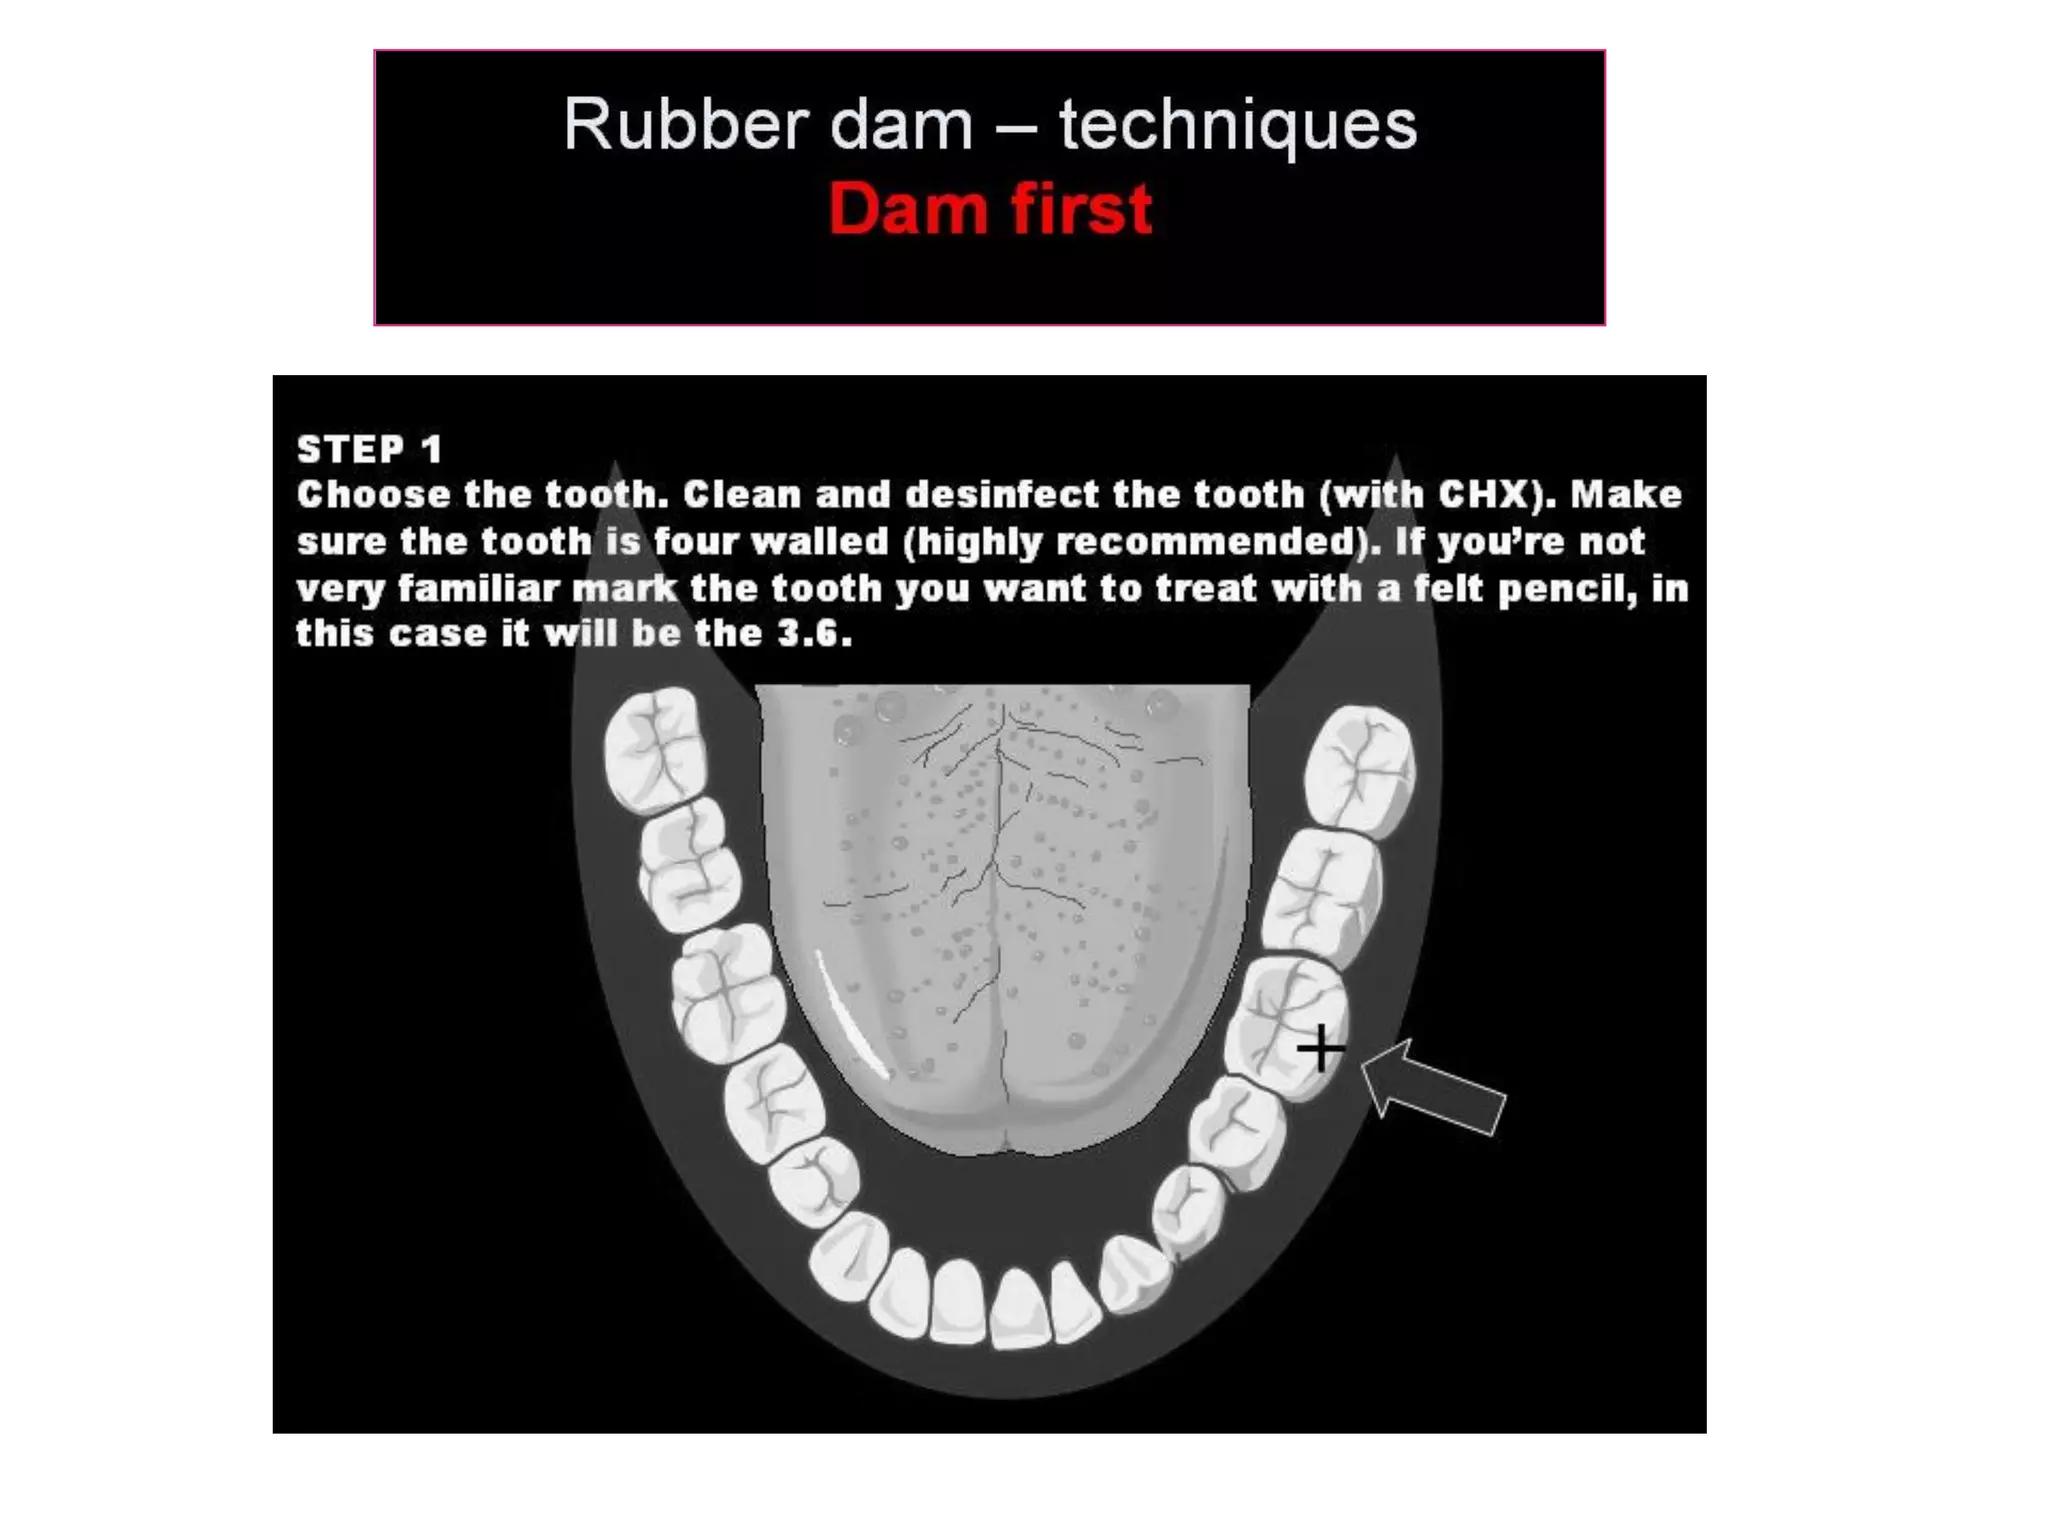

This document discusses the materials and components used for rubber dam isolation in dentistry. It describes the different types of rubber dam materials including color options and napkins to absorb moisture. It also outlines the tools needed such as punches to make holes, templates and stamps to guide hole placement, clamps to secure the dam, and other accessories like wedges and lubricant. Finally, it provides guidance on punching holes for different types of teeth and properly placing clamps in the rubber dam.